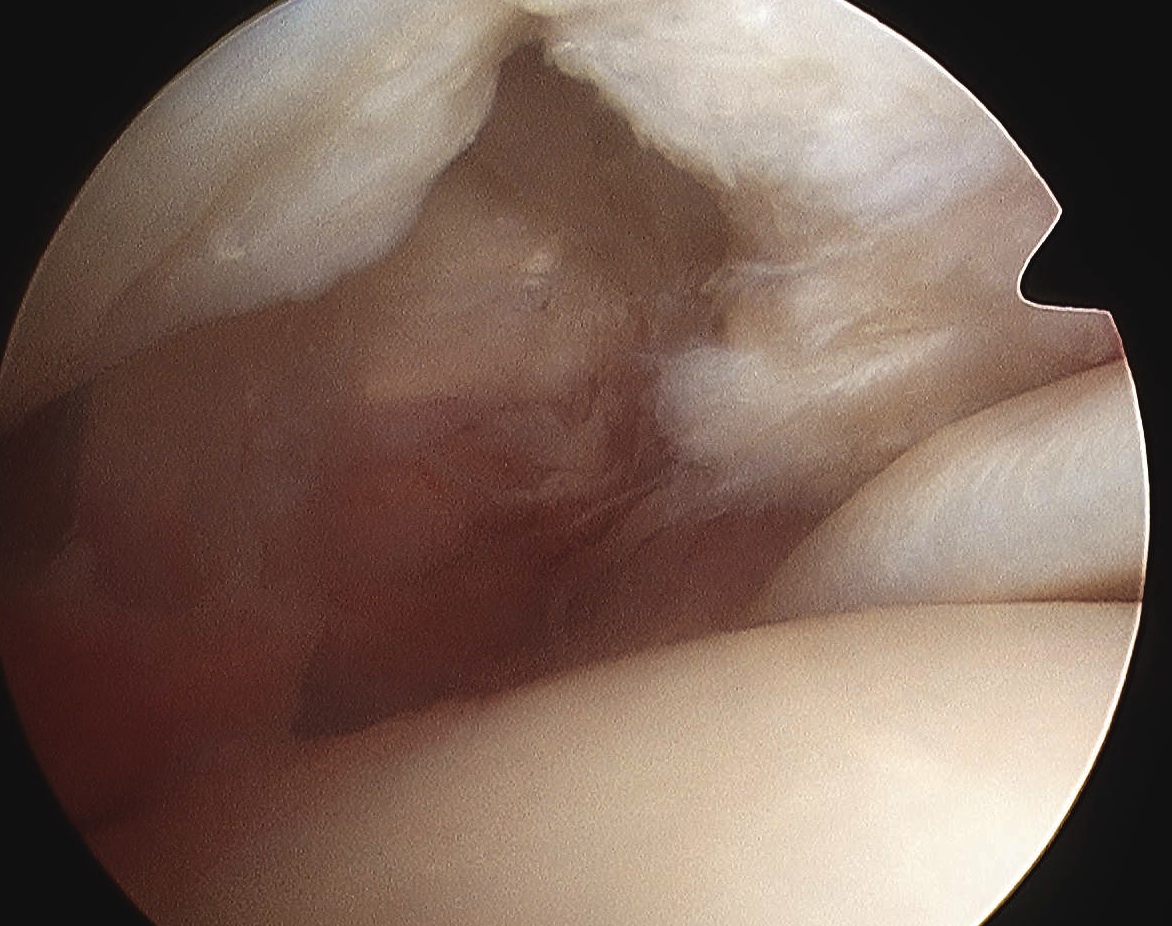

PVNS

Definition

Pigmented Villo-Nodular Synovitis

- benign inflammatory process that arises in synovial tissues

- contains significant amounts of hemosiderin

A. Diffuse

- throughout joint synovium

- more difficult to treat / excise fully